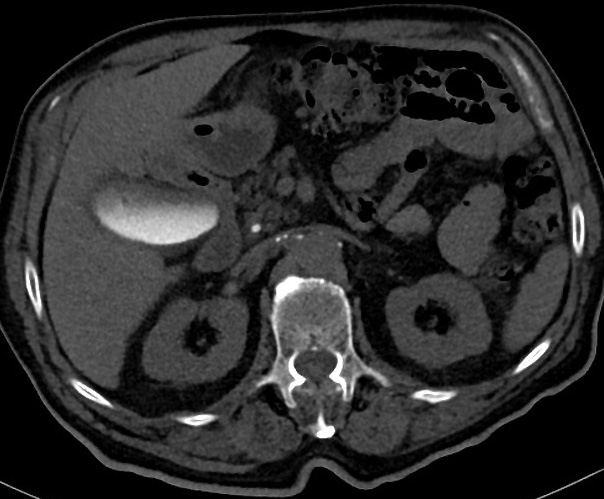

| |

|

Image TDM du foie et de la

vesicule biliaire en coupe

axiale ( avec contrast iode intra veineuse ) . |

Image TDM en coupe

axiale a travers la vesicule biliaire ( avec

contrast ) . Vesicule biliaire sont en

voyait |

Image TDM de l'abdomen en

coupe coronale ( frontale)apres recontruction

saciale avec contrast iode . La vesicule biliaire

est en vue |

Aspect normale de la

vesicule biliaire et de la veine

porte commun en coupe TDM coronale . |